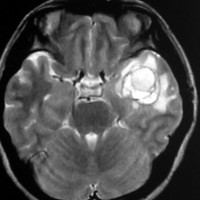

出血が溶けて少し小さくなっています。海綿状血管腫の周りには黒い縁取りがあります。この黒い部分は血液が溶けて残った鉄が脳の中にたまったことを示しています(siderosisといいます)。この鉄のしみ込みはけいれんの原因になると考えられます。この海綿状血管腫は中等度の大きさですが,治療が難しいほどのてんかんが無ければ手術などしないでほっておいてもいいです。手術で側頭葉(特に海馬)を損傷すると記憶の障害などもでます。

脳血管撮影の静脈層です。 血管腫の内側に刷毛で掃いたような異常な静脈が見えます。これは静脈性血管腫といって,大きな海綿状血管腫にはよく合併する異常です。海綿状血管腫をとるときに誤ってこの静脈性血管腫を傷つけてしまうと,静脈梗塞が起きるので注意しなければなりません。このケースの場合はもし損傷すると左側頭葉内側の脳損傷になります。